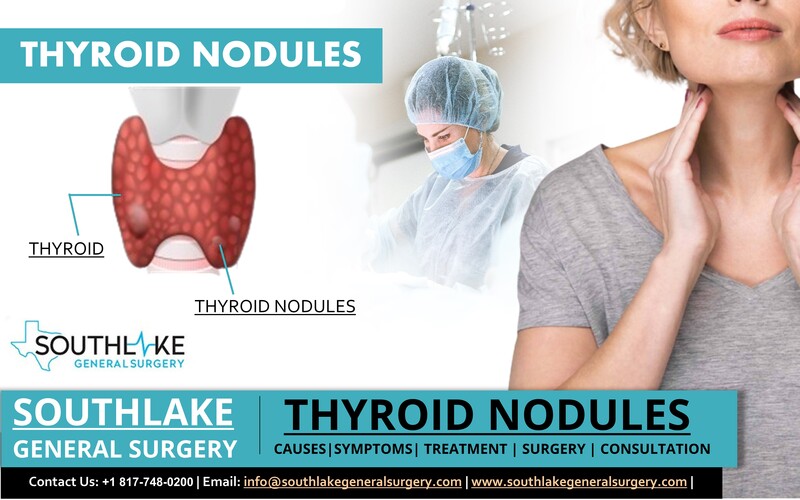

Thyroid Nodules Diagnosis Archives Southlake General Surgery

https://www.southlakegeneralsurgery.com/wp-content/uploads/2021/12/Thyroid-Nodules-Symptoms-Treatment-and-Surgery.jpg

Thyroid Nodules

Thyroid Nodules